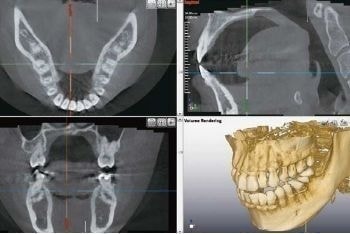

レントゲン装置には、レントゲン写真を3Ðで診断できるCTを採用し、歯の悪いところの診断も断面から診査出来ますので、平面で診査するよりも格段に悪いところを正確に把握することが可能となります。